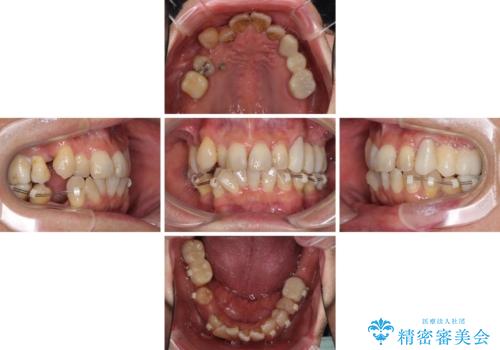

初診時に4年かかりますとお伝えし、実際に4年数ヶ月を要する治療となりました。

治療中は仮歯が頻繁に脱落したり、歯周外科によりむき出しとなった歯根が知覚過敏を起こしたりと、苦労は絶えませんでしたが、4年の治療の後にスッキリと仕上げることができました。